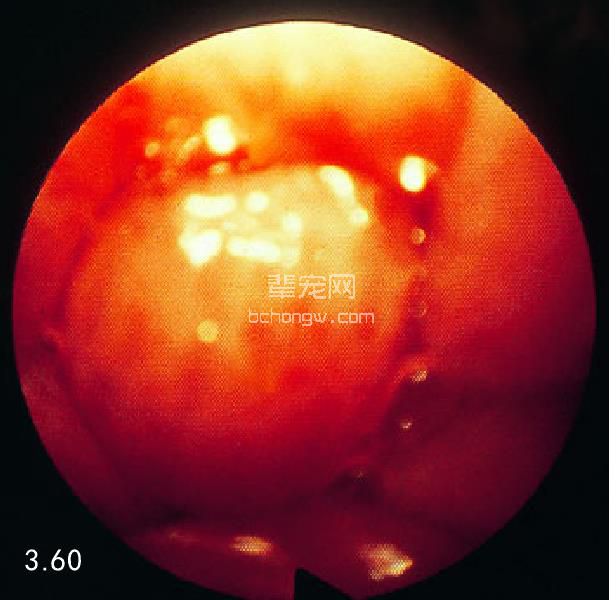

病因学 病因包括狭窄、异物、肿瘤以及较少见的憩室和胃食管套叠。原发性食管肿瘤包括平滑肌瘤、癌 和肉瘤(图3.60~图3.63)。有一篇报道称转移性甲状腺肿瘤是最常见的食管肿瘤。胃前部的癌症也可能影响到 食管下括约肌和后段食管。酸性物反流(特别是麻醉期间)、食管异物取出后的狭窄是造成食管狭窄的主要原 因。对于犬和猫来说,最常见的食管异物是骨头。食管憩室是由食道内力(异物)破坏食管完整性后形成的。 最容易出现憩室的位置是胸腔入口和膈上的区域。

图3.60 一只13岁的巴赛特猎犬胃底部的硬腺癌已经侵入食管远端,导致食管阻塞和继发的食管扩张。